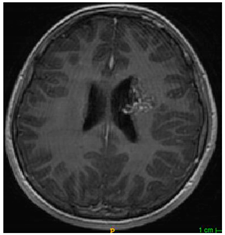

Table 4. Predictions with high dice scores.

Ground truthDeconvNetDeepMedic

Applsci 11 09180 i013 Applsci 11 09180 i014 Applsci 11 09180 i015

PSPNetU-NetV-Net

Applsci 11 09180 i016 Applsci 11 09180 i017 Applsci 11 09180 i018